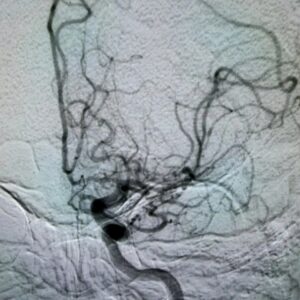

Un patient atteint d’un anévrisme de l’artère cérébrale moyenne a récemment bénéficié d’une prise en charge hautement spécialisée à l’Hôpital de l’Amitié Sino-Guinéenne (HASIGUI), confirmant le rôle de l’établissement comme référence en neurochirurgie en Guinée.

Grâce aux équipements de pointe du centre diagnostique, l’anévrisme a été identifié avec une précision remarquable, ouvrant la voie à une planification thérapeutique rigoureuse et sécurisée. L’intervention chirurgicale, menée par le Dr Ibrahima Sory Souaré et son équipe, a consisté en un clippage microchirurgical, réalisé avec succès.